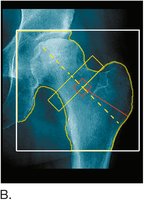

Bone Densitometry

Bone densitometry (DEXA scan) measures bone mineral density to assess osteoporosis risk.

Common sites: hip, spine, wrist

Results help guide treatment decisions